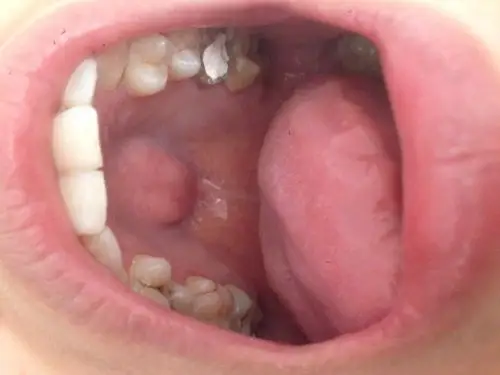

最近补牙时医生说我上颚和别人不一样我才知道,一直以为它就是这样的